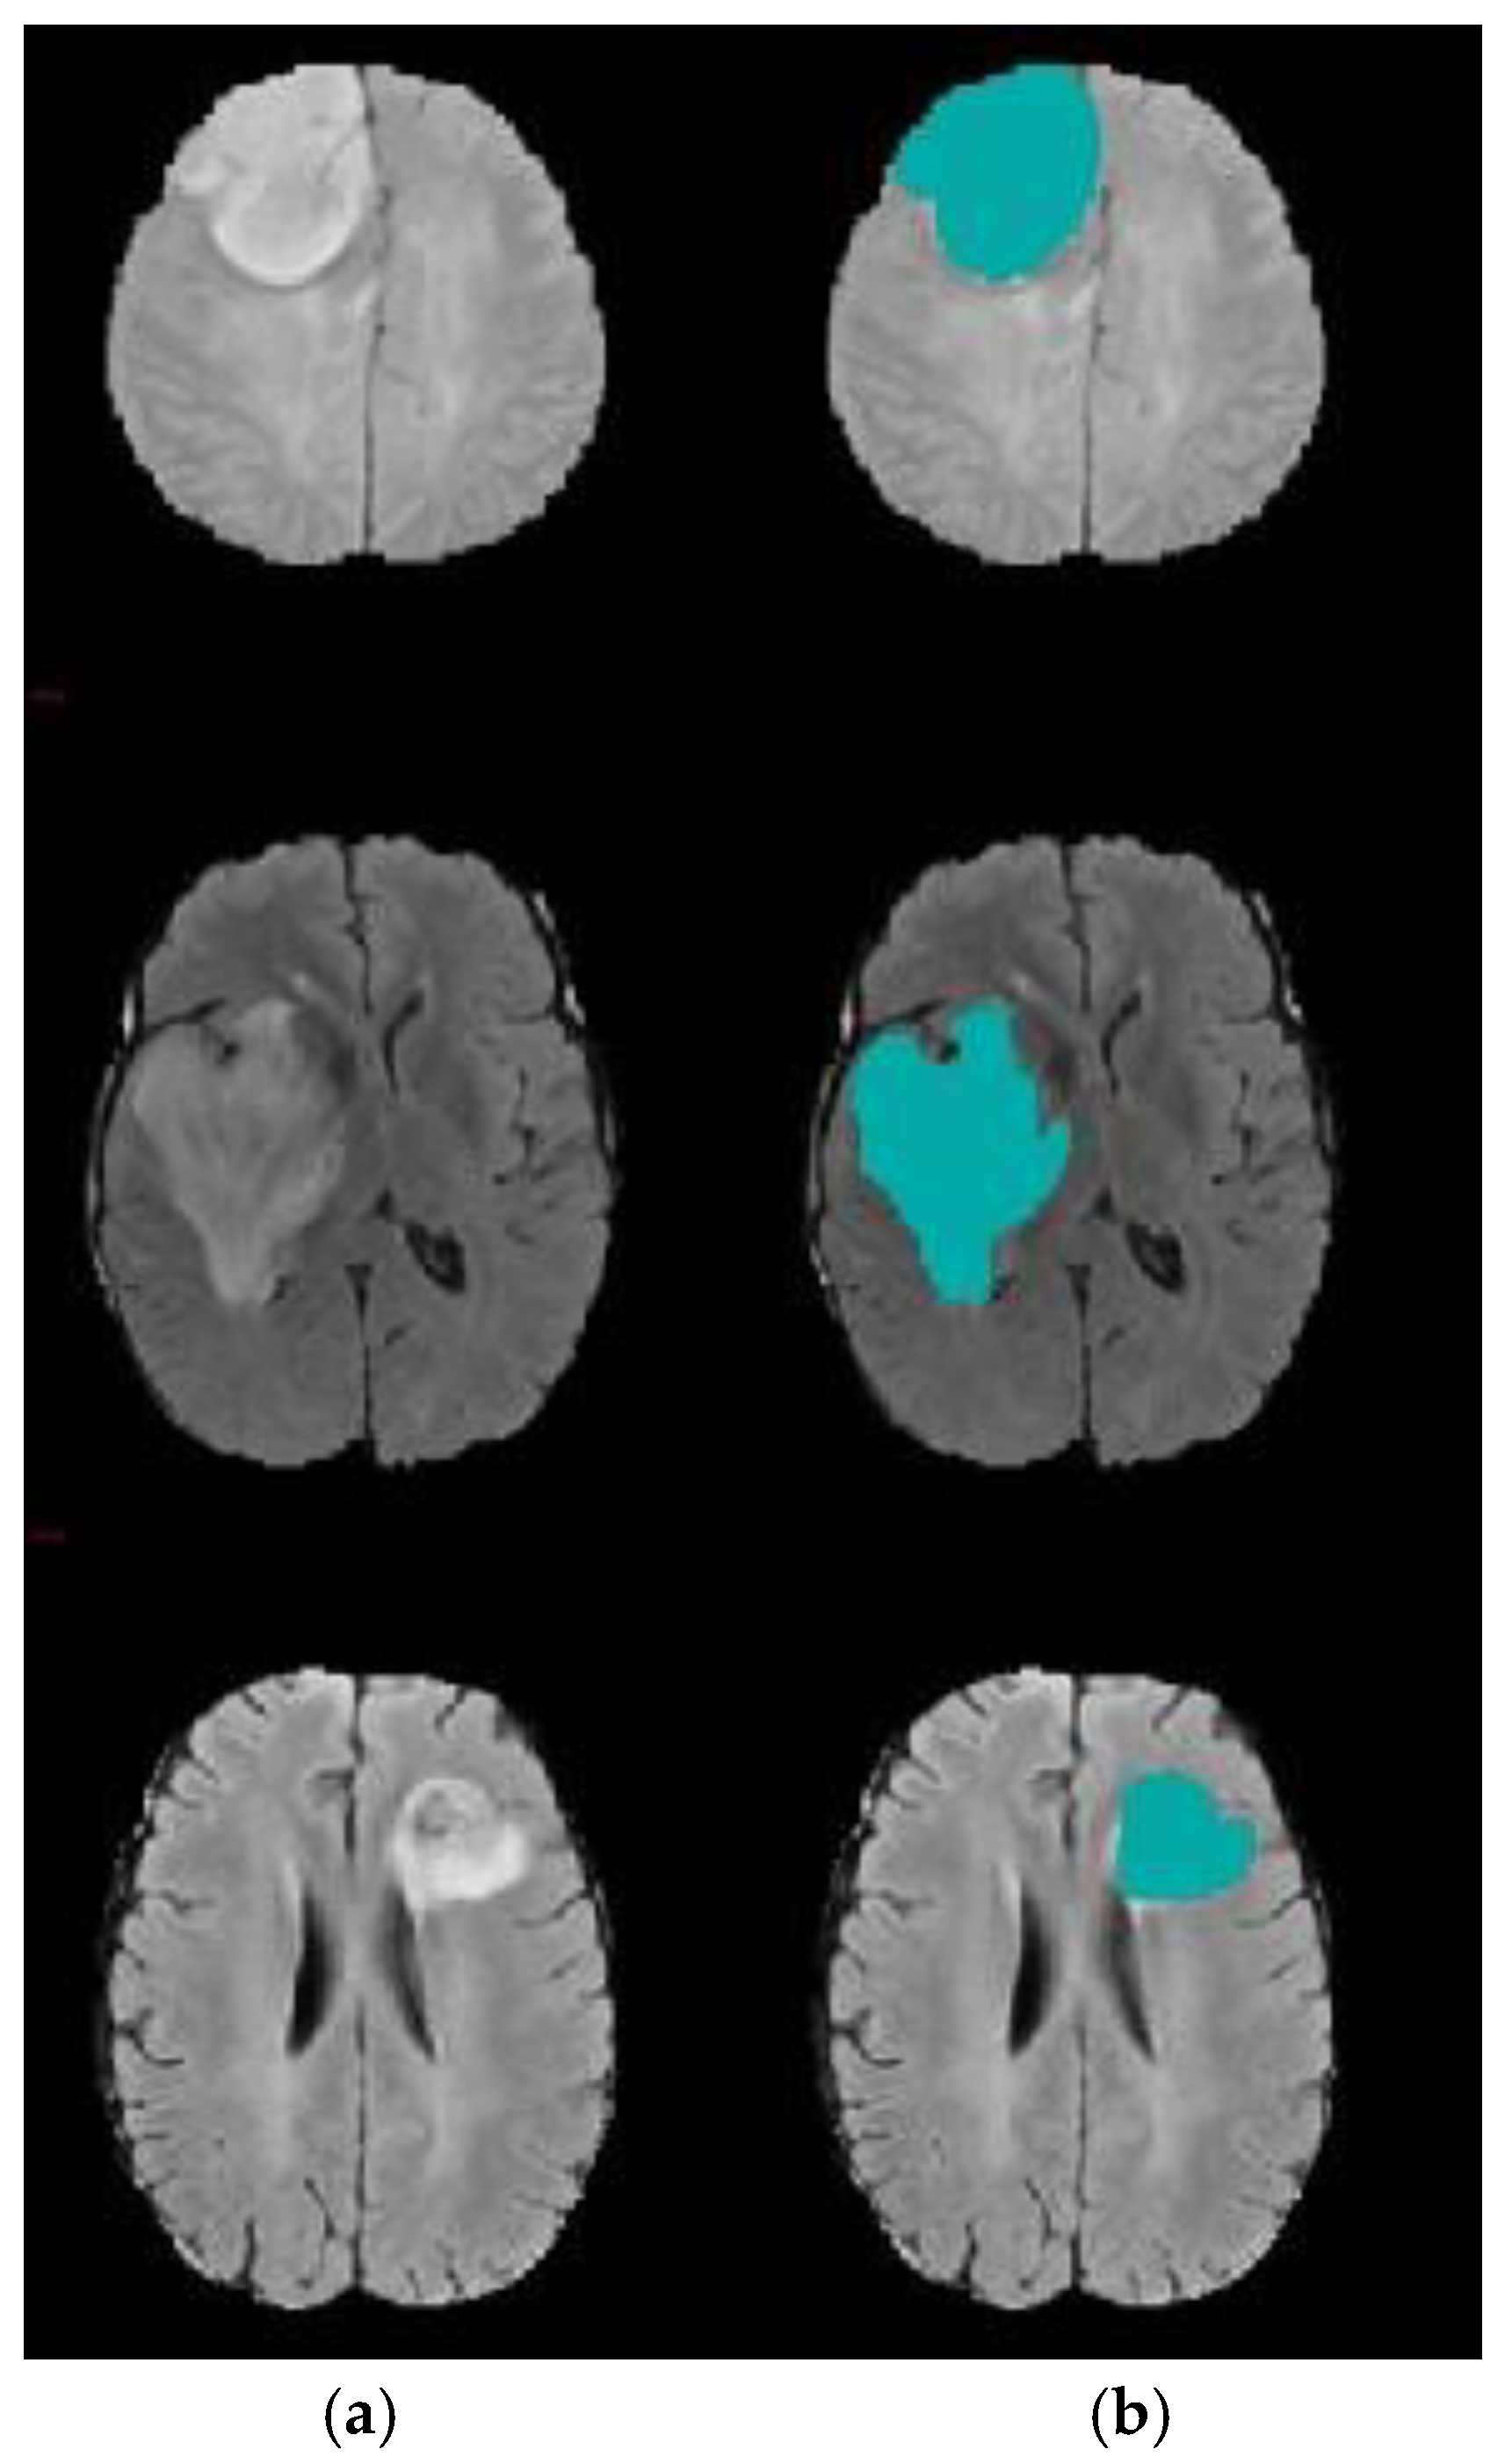

The goal of this experiment was to emphasize the role of DA in reducing the level-set segmentation iteration number. Herein, to reduce time cost and increase accuracy, the initial contour of the region of interest (ROI) target was automatically generated based on the two-step DA clustering result. Table 5 shows the comparative results of the suggested model and traditional level set segmentation algorithms in terms of the number of iterations required for level set to complete the segmentation process. These group of experiments were conducted 10 times to ensure the robustness of the proposed model against random factors, which may affect the stability of the algorithm. Herein, five MRI volumes were randomly chosen. It can be inferred that utilizing the DA algorithm reduces the number of level set iterations dramatically. Using the best-designed two-step DA parameters, the contour was positioned very close to the tumor region. Figure 10 and Figure 11 show a sample of the segmentation process using the modified level set.

Figure 10.

Brain tumor segmentation for BRATS 2017 dataset. (a) 2D slice. (b) Final segmentation with the modified level set.

Figure 11.

Brain tumor segmentation for BRATS 2017 dataset. (a) 2D slice. (b) Final segmentation with the modified level set. (c) Ground truth.